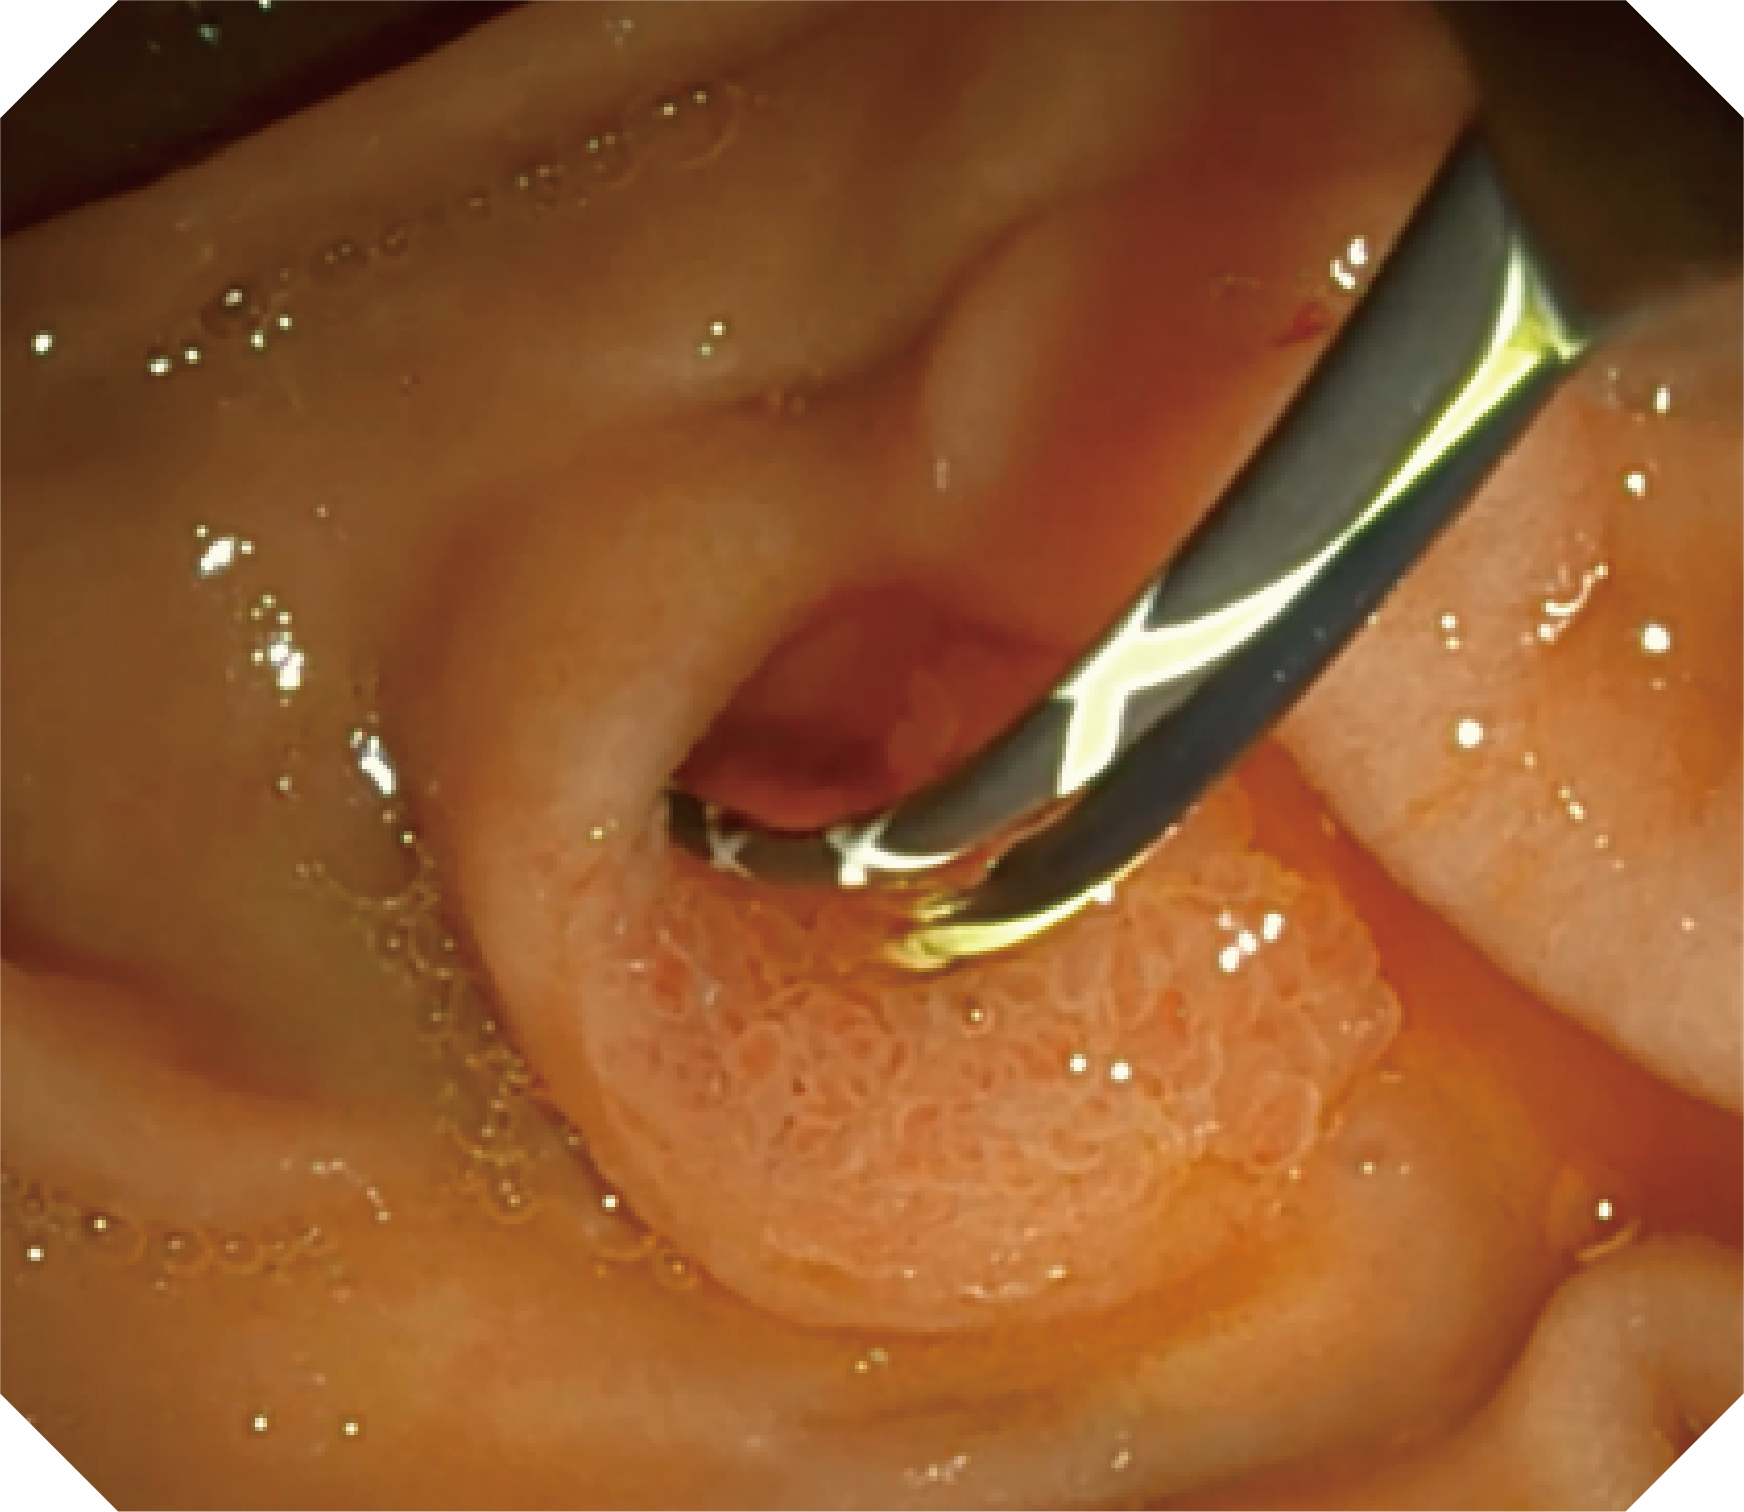

CMOS传感器提供高清内镜视野 SFI/VIST光学染色技术凸显病变区域

4.2mm大钳道,器械交换更顺畅

优异的手术器械抬举性